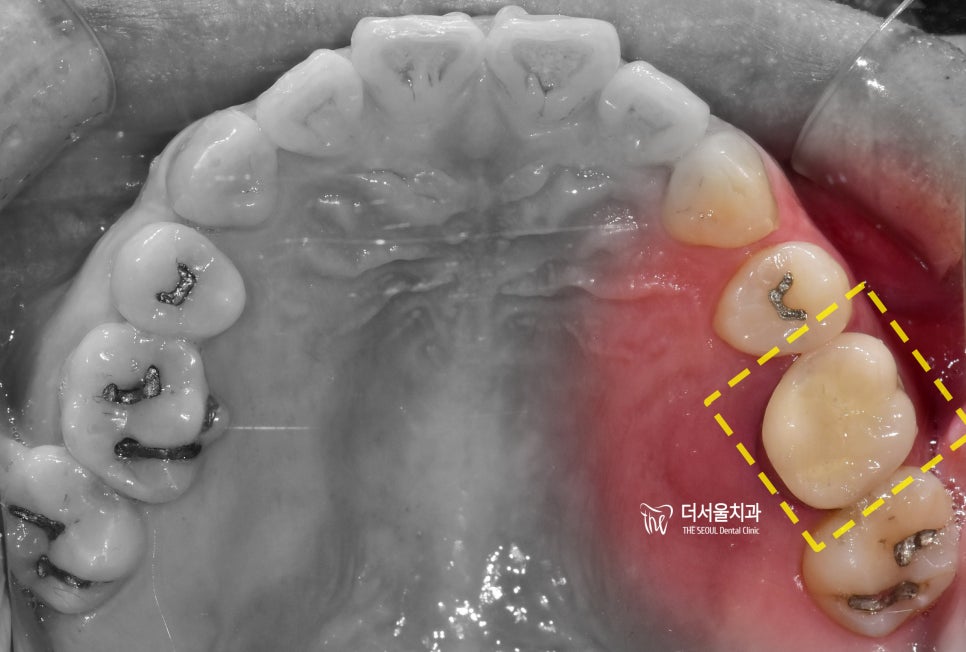

엑스레이를 보면, 한쪽 어금니가

썩었으며 뿌리 끝에는 염증이 맺혀있는

apical lesion 을 관찰 할 수 있고

주위 치조골 또한 많이 위축이 되어서

아래로 내려가 있는 것을 볼 수 있습니다.

근데 또 겉으로 봤을 땐 멀쩡합니다.

크게 문제가 있는거 같진 않죠?

이게 문제입니다.

역시나, margin 쪽으로 우식증들이

넓게 퍼져있는 것을 볼 수 있었고